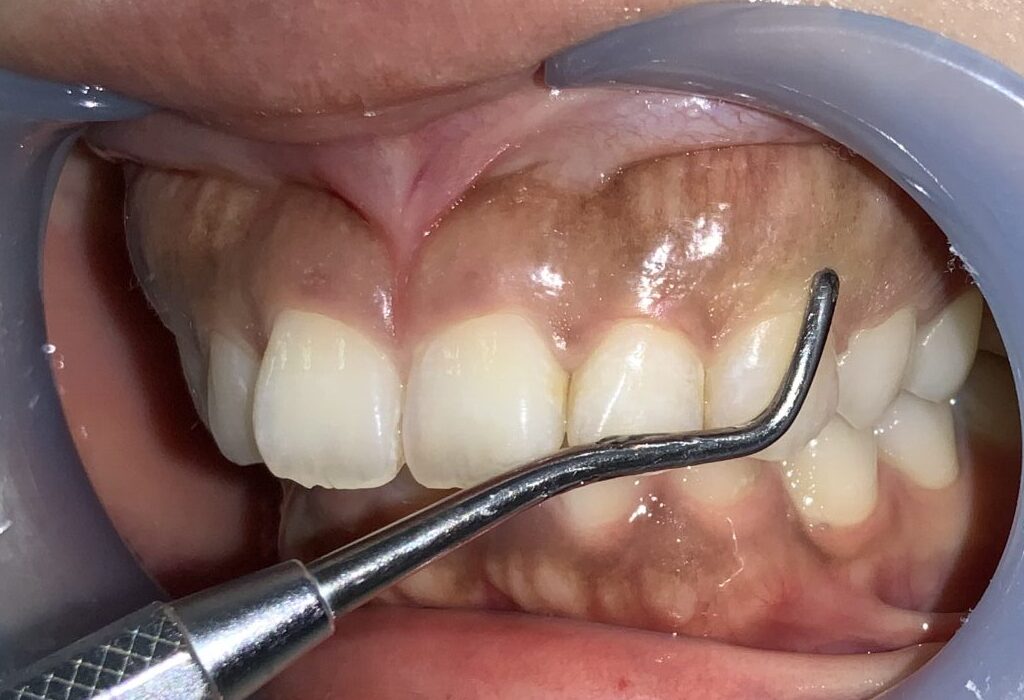

まずは手術前の状態です。

歯に歯ぐきがたくさんかぶっている状態です。

まずは歯ぐきのかぶり具合、歯ぐきの厚み、歯槽骨の状態、歯ぐきの切除範囲の検査からです。

このくらいかぶっていますから、綺麗に切除できます。